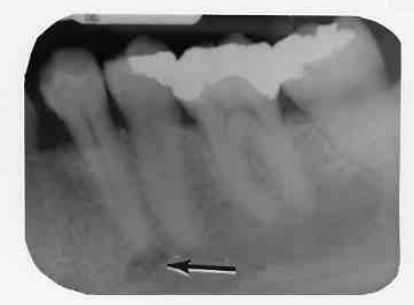

3. What is the anatomical structure indicated by arrow in this radiograph?